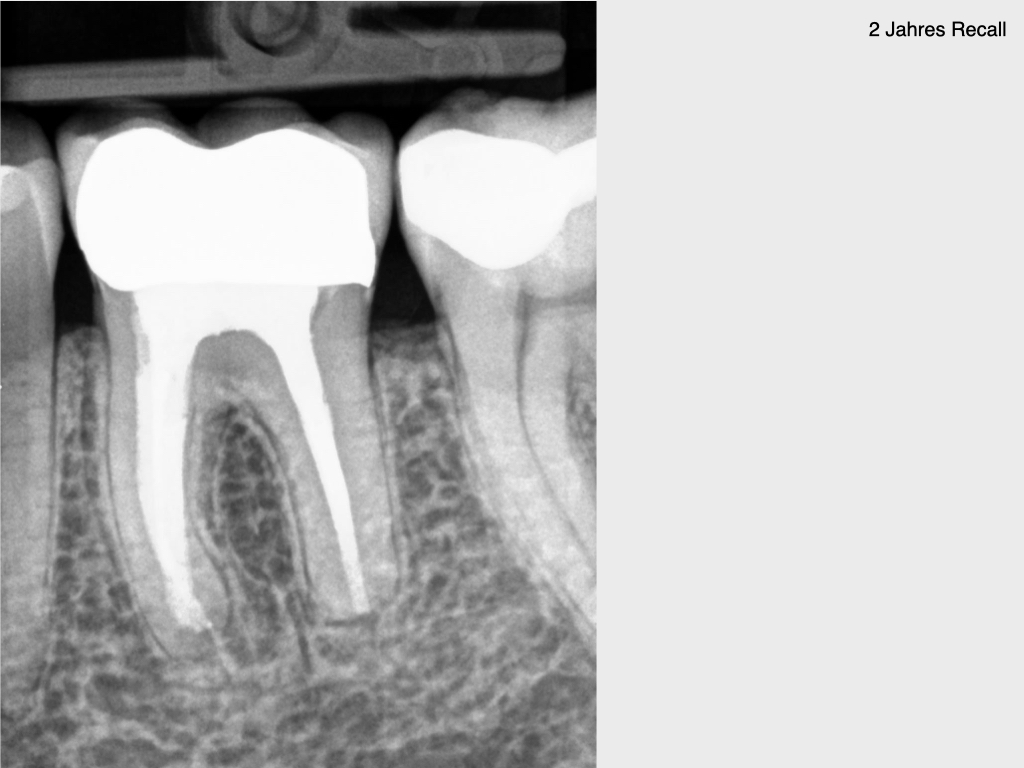

10 Jahres Recall